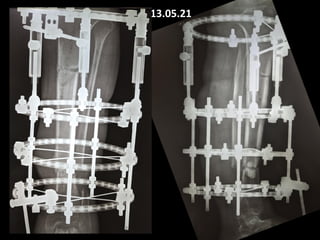

13.05.21